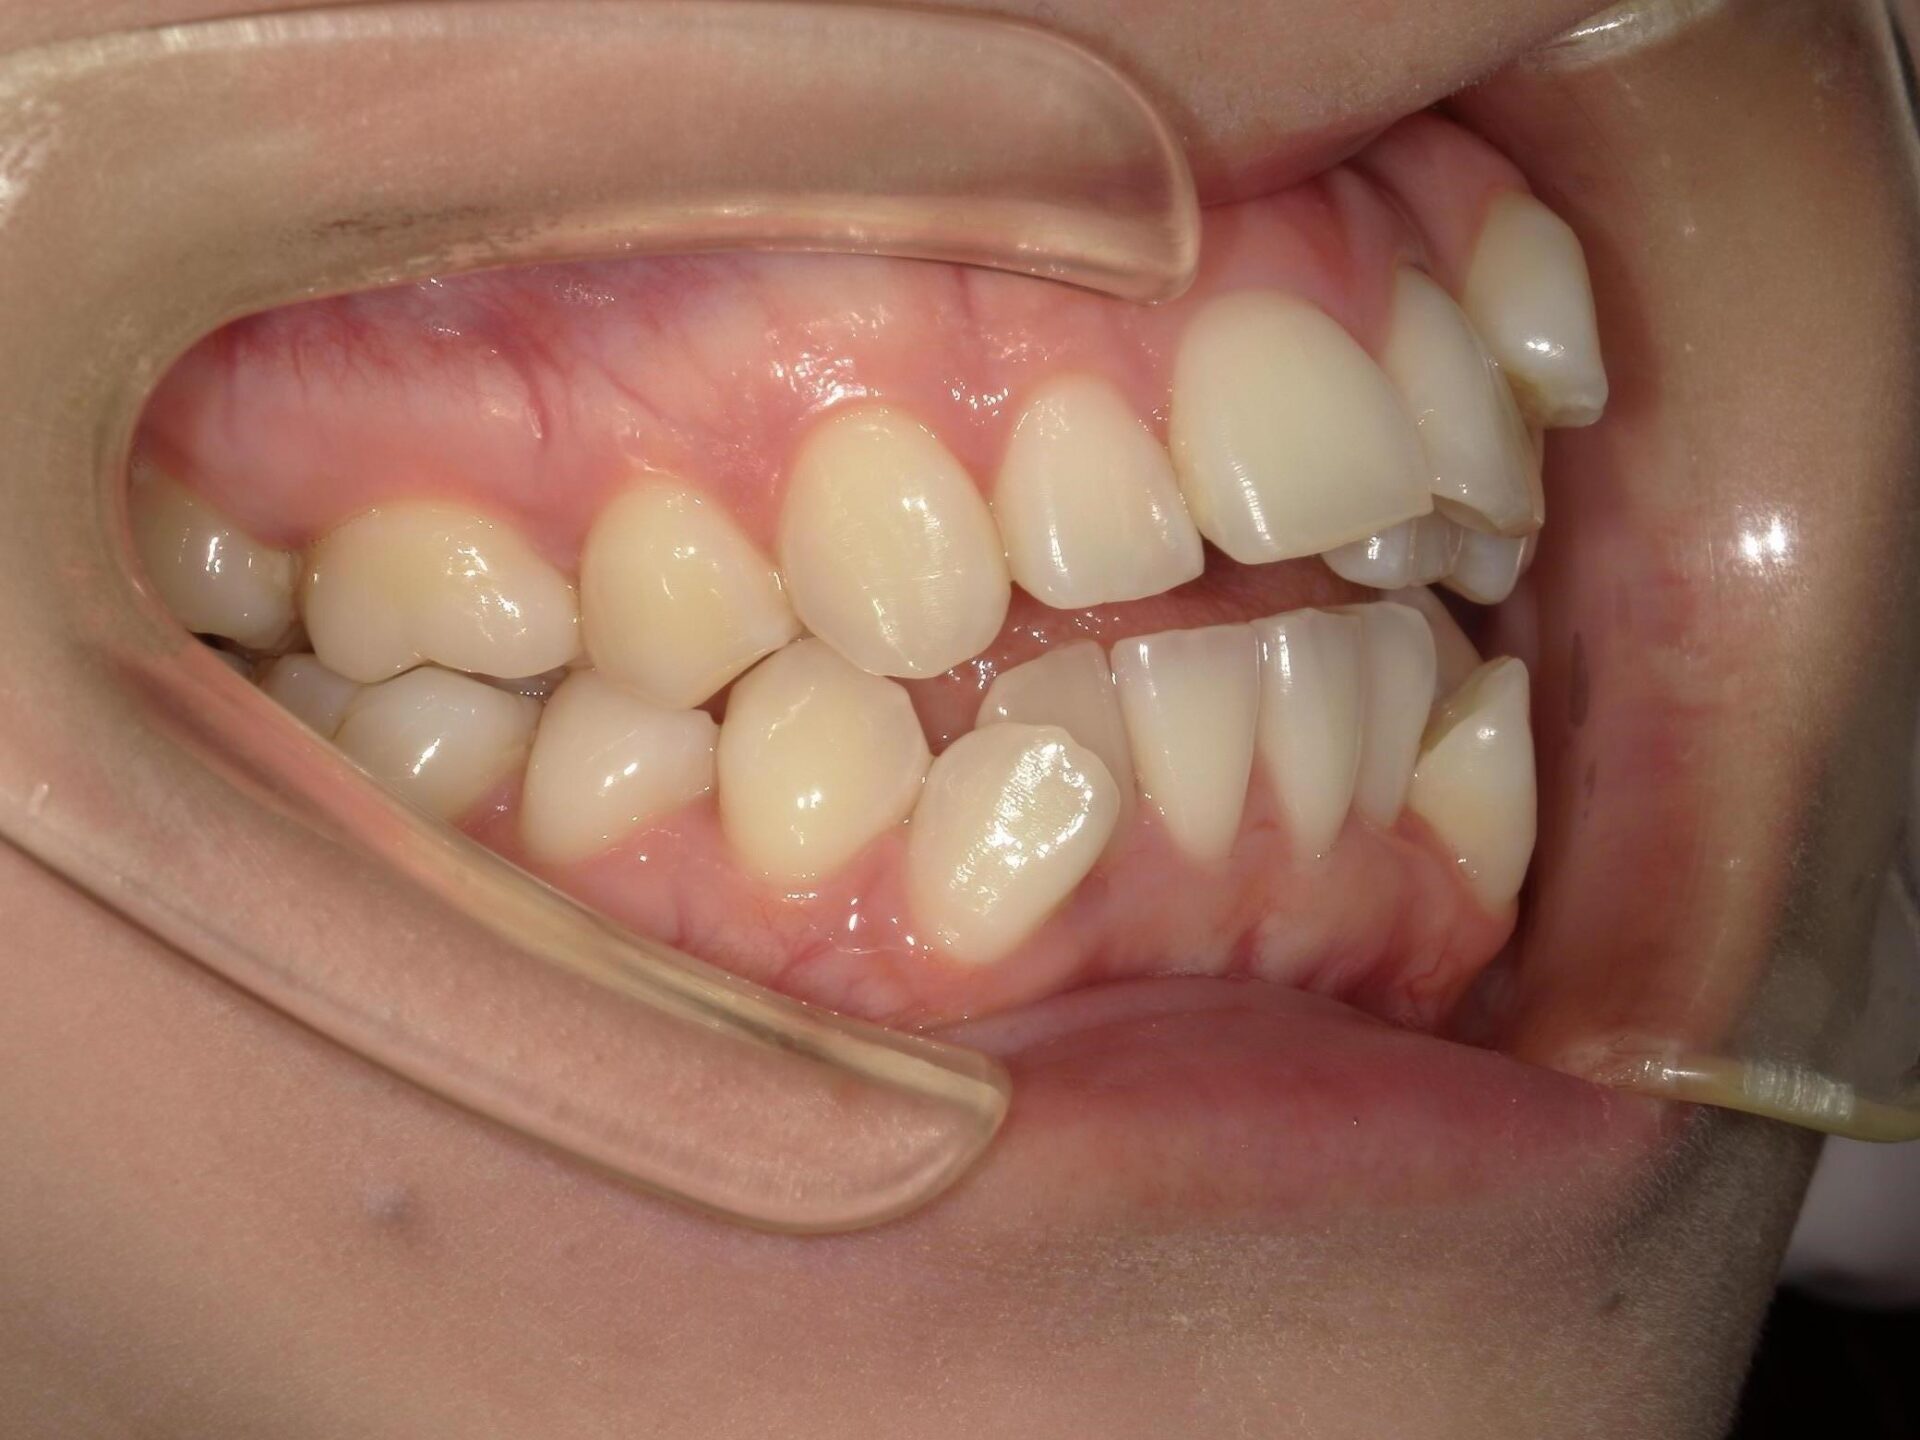

20代、女性、ワイヤー

| 施術内容 | 主訴:全体的に凸凹が気になる 詳細:ワイヤー矯正での歯並び改善 ずっと磨きにくく、臭いが気になっていましたが、 矯正後は磨きやすくなり、臭いも無くなって満足された症例です。 |

|---|---|

| 治療期間 | 16ヶ月(3/13現在 治療終了) |

| リスク・副作用 | ■リスク・副作用 ・治療の初期段階では、痛みや不快感が生じやすくなりますが、一週間前後で慣れます。 ・歯の動き方には個人差があるため、予想された治療期間より延長する場合があります。 |

| 費用 | ワイヤー矯正 60万円(税込660,000円) |